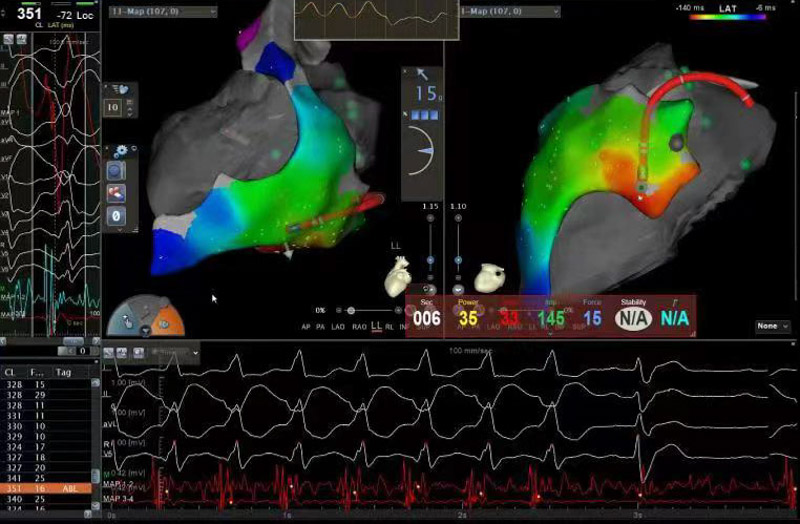

心外膜室性心動過速行射頻消融術(shù)這項技術(shù)是心包腔內(nèi)無積液的情況下,經(jīng)胸壁進(jìn)行干性穿刺后,將標(biāo)測及消融導(dǎo)管送到心包腔內(nèi),再進(jìn)行定位消融異常的心電病灶,手術(shù)風(fēng)險大、標(biāo)測復(fù)雜、技術(shù)難度高,需要團(tuán)隊具備極高的心包穿刺及導(dǎo)管操作技術(shù)。

為確保手術(shù)安全,心血管內(nèi)科電生理團(tuán)隊準(zhǔn)備了詳盡的手術(shù)方案和應(yīng)急預(yù)案。手術(shù)當(dāng)日,北京安貞醫(yī)院心血管內(nèi)科蔣晨曦教授親臨指導(dǎo),在ICE及X線引導(dǎo)下,精確地將導(dǎo)絲通過心包干性穿刺途徑到達(dá)心外膜,再通過動靜脈途徑到達(dá)心內(nèi)膜,采用心內(nèi)膜聯(lián)合心外膜進(jìn)行標(biāo)測及消融。放電3秒后室性心動過速終止,鞏固消融120秒,并在靶點附近鞏固放電多次,經(jīng)過一段時間觀察,無室性心動過速再發(fā),手術(shù)順利結(jié)束。術(shù)后患者癥狀解除,復(fù)查動態(tài)心電圖顯示無室性心律失常再發(fā),目前陶先生已成功康復(fù)出院,門診隨訪也一切良好。